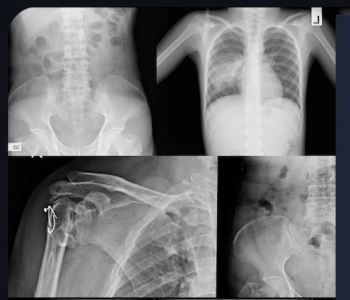

An emerging deep learning algorithm had a lower AUC and sensitivity than urological radiologists for differentiating between small renal masses on computed tomography (CT) scans but had a 21 percent higher sensitivity rate than non-urological radiologists, according to new research.